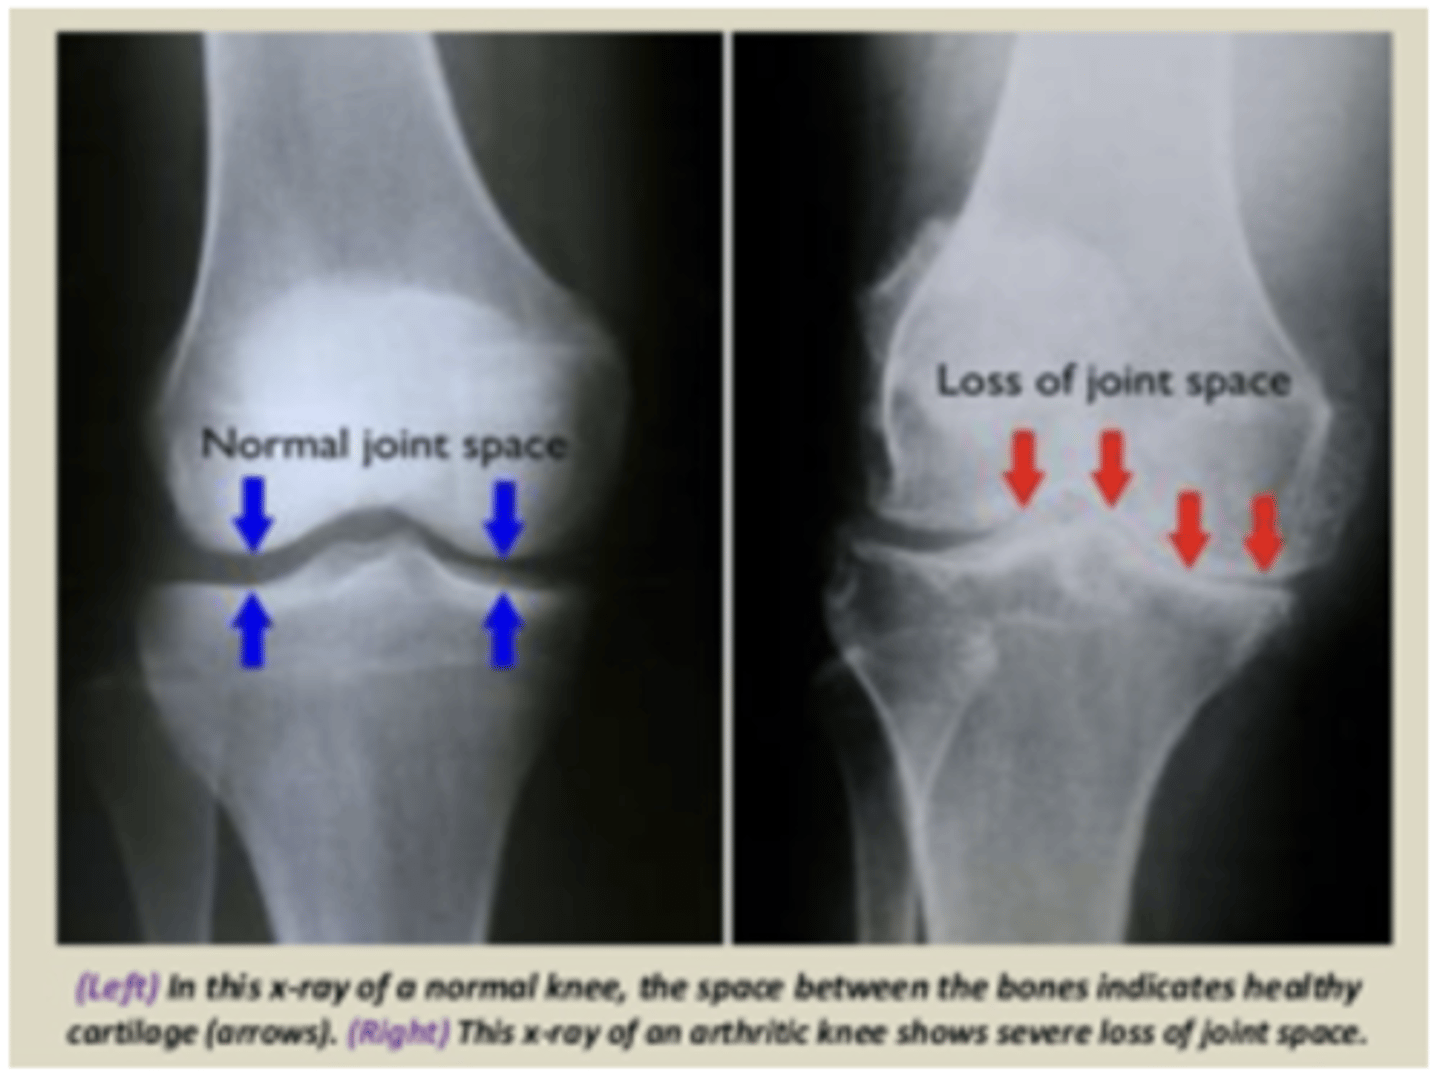

osteoarthritis (OA)

Loss of cartilage in synovial joints

Damaged joint cartilage tries to heal itself

-- Creating osteophytes or spurs

-- Cartilage contains more water, less collagen

-- Cartilage becomes weak, rough, eroded

Healthy cartilage (knee)

Osteoarthritic cartilage (knee)